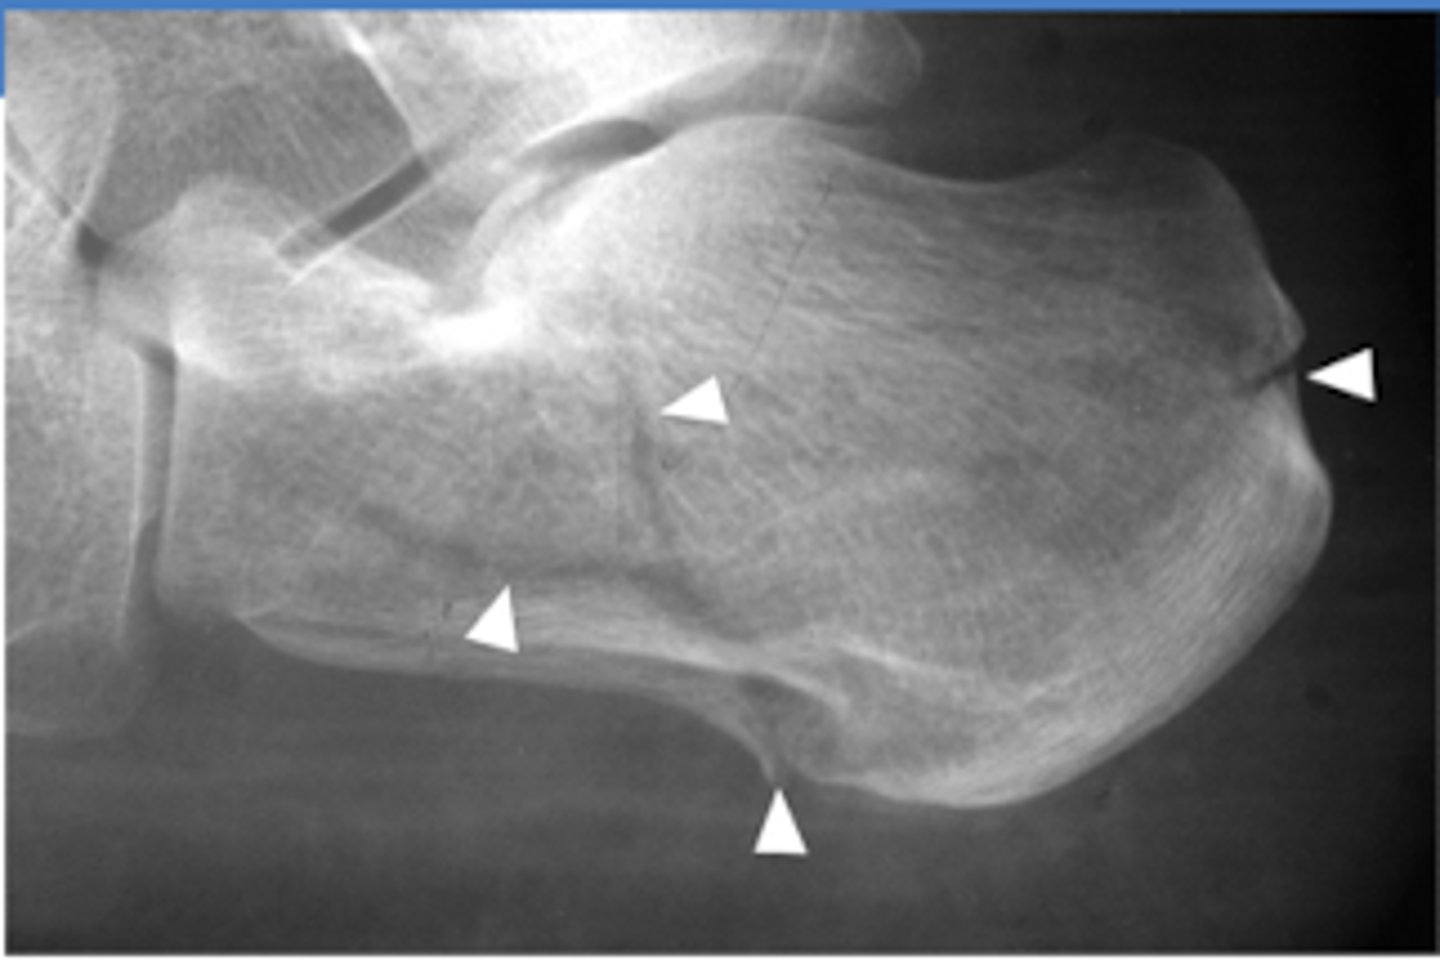

What is Chopart's Fracture-Dislocation?

Dislocation of the mid-tarsal joints (talonavicular + calcaneocuboid)

Fracture of the calcaneus, cuboid and navicular

What is the treatment for Chopart's Fracture-Dislocation?

open reduction w/ internal fixation